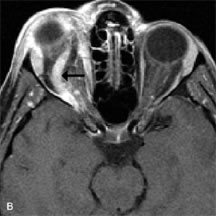

PATIENT PREPARATION Before MRI is performed, patients must be screened and prepared to avoid the potential hazards associated with the strong magnetic field. Patients who have ferrous aneurysm clips or cardiac pacemakers, who depend on life-support equipment, or who retain a possible metallic intraocular foreign body are not candidates for this imaging modality. MRI cannot be performed on obese patients who cannot fit into the bore of the magnet. Patients who are claustrophobic may not tolerate a prolonged period of study within the confines of the magnet, whereas others might do well if given a mild sedative. All worn metallic objects (e.g., necklaces, watches) should be taken off, credit cards set aside, and eye makeup removed before entering the room containing the magnet.5,20,34,35,36 NORMAL ORBITAL ANATOMY T1-weighted images provide the best anatomic details of the orbit because they display superior contrast resolution between normal structures (see Fig. 8). The vitreous has a long T1, resulting in an intermediate signal similar to brain, whereas the crystalline lens and sclera appear dark because of a longer T1 and short T2. The extraocular muscles, like all skeletal muscles, demonstrate a moderately long T1 and short T2 and highly contrast with the intense signal of the surrounding orbital fat (adipose tissue has an extremely short T1). The lacrimal glands appear as mottled areas of reduced intensity of the signal from the orbital fat in the lacrimal fossa. The optic nerves are seen with the same signal intensity as brain white matter and are hypointense relative to the orbital fat because their Tl is longer than the Tl of fat but shorter than the Tl of water. Cortical bone is not well delineated because it contains little free water, yielding minimal signal in MRI, and thus appears dark on all pulse sequences. This feature explains why MR images of the orbital apex and intracanalicular portion of the optic nerves are superior to comparable CT scans. Partial volume averaging of the bones in these regions obscures soft tissue details on CT images, whereas MRI reveals the signals only from the soft tissue structures with no cortical bone input. Bone marrow, on the other hand, is seen as a relatively intense signal because of its high fat content (see Fig. 8).37,38 T2-weighted pulse sequences are not ideal for imaging normal anatomy; however, they are particularly useful in revealing pathologic conditions (see Fig. 9). T2-weighted studies are most easily recognized by a bright vitreous signal. ORBITAL DISEASES Vascular Lesions Cavernous hemangiomas appear as well-circumscribed, smooth, usually intraconal masses that are isointense to muscle on T1-weighted images and hyperintense on T2-weighted images (Fig. 12). Patchy early enhancement is typically followed by diffuse, more homogeneous enhancement.39 The internal architecture of the mass, including septation and internal vasculature, may often be appreciated with high-quality orbital imaging.40 Lymphangiomas consist of ectatic vascular channels within a connective tissue stoma with varying degrees of lymphoid cellularity. On MRI, these tumors are typically poorly circumscribed, multicompartmental, and heterogeneous, often showing cystic dilations with fluid levels (Fig. 13). The signal characteristics within lymphangiomas vary considerably, reflecting cystic and solid components and the varying paramagnetic characteristics of blood at different stages of degradation.40–42 Acute hemorrhage appears hypointense on both T1- and T2-weighted formats. Methemoglobin present in subacute hemorrhage (3 to 14 days) leads to hyperintense signal on both T1- and T2-weighted images.41 A small percentage of lymphangiomas appear radiologically indistinct from orbital cavernous hemangiomas.43 Orbital varices are venous malformations that expand with increased systemic venous pressure, such as with Valsalva maneuvers. Because rapid acquisition of images during a Valsalva maneuver is important in imaging such a lesion, conventional or spiral CT is currently the modality of choice.44 MRI is an excellent modality for demonstrating enlargement of the cavernous sinus and dilation of the superior ophthalmic vein in patients with high-flow carotid-cavernous fistulas (Fig. 14).37MRA may be helpful in the evaluation of the venous outflow pattern. The rapidly flowing blood in these vascular structures carries the excited protons out of the section before they can be imaged, resulting in their dark appearance.5 In low-flow dural arteriovenous malformations, MRA may help define the arterial feeding vessels.45 Neural Lesions MRI is more effective than CT in delineating the intracranial optic nerves, chiasm, and optic tracts and, for this reason, is the preferred imaging modality in the evaluation of optic nerve disorders. The spatial relationships and image contrast of the orbital tissues with intraorbital optic nerve tumors is comparable between the two imaging modalities. The normal nerve is isointense to brain and appears enlarged and kinked owing to infiltration of an optic nerve glioma on T1-weighted images. Gliomas appear hyperintense on T2-weighted images and may be heterogeneous owing to cystic areas within the tumor. Contrast enhancement is variable.46 Intraorbital and intracranial optic nerve sheath meningiomas are usually isointense to cortical gray matter on Tl-weighted images and remain isointense on proton density studies (Fig. 15). Gd-DTPA is useful in delineating the intracranial extension of optic nerve meningiomas.7,47 The hyperostosis of bone and calcification associated with meningiomas are not demonstrated as well on MRI studies as on CT scans.20,37 Gd-DTPA–enhanced MRI also appears promising in the study of the permeability of the blood–brain barrier in selected optic neuropathies.22,48 MRI may reveal an enlarged optic nerve and some degree of contrast enhancement in cases of optic neuritis.49 Muscle Disorders Extraocular muscle enlargement in patients with thyroid-associated orbitopathy is demonstrated equally well with CT and MRI studies. However, the superior tissue contrast on MR images reveals better details of the relationships of the optic nerve to the thickened muscles at the orbital apex (Fig. 16).50 In addition, MRI may be able to differentiate between muscles that are enlarged as a result of edema and active inflammation and those enlarged because of fibrosis by their T2 relaxation times.21 Quantitative MRI was not found to be accurate in predicting the success of low-dose orbital irradiation.51 However, a muscular index relating the diameters of the rectus muscles to the bony orbital dimensions was useful in predicting optic nerve compression.52 MRI is also effective in imaging orbital tumors of mesenchymal origin, such as rhabdomyosarcoma, particularly in the assessment of extension into the anterior and middle cranial fossae (Fig. 17).37 The lack of any pathognomonic radiologic features necessitates rapid orbital biopsy when rhabdomyosarcoma is suspected. Osseous Lesions In general, CT is the imaging modality of choice when details of quantity and quality of bone are needed; however, abnormalities of bones can be detected indirectly by MRI. Cortical bone appears black (signal void) on MR images because of its low proton density and free-water content. The absence or discontinuity of the signal void of the orbital walls may represent bony destruction or fracture. Hyperostosis associated with prostate metastases or meningioma is visualized as areas of black smudging.50,53 Diseases in which the bone is replaced by pathologic tissues with a high free-water content, such as fibrous dysplasia, are well demonstrated on MRI. An intermediate signal intensity on T1-weighted images and hypointense signal on T2-weighted images is representative of fibrous dysplasia. Enhancement on post–Gd-DTPA MR scans is seen and is more evident in areas that are less mineralized.54 Cystic Lesions Dermoid cysts appear as rounded, well-defined lesions typically contiguous with an orbital bony suture. The high-intensity signal on T1-weighted images is attributed to the sebaceous-produced lipid contents (Fig. 18).31,50 Mucoceles may demonstrate a hypointense or hyperintense signal on MR images, depending on the concentration of proteinaceous or inflammatory fluid components. The integrity of the bony walls of the expanded sinus cavities cannot be assessed on MR as well as by CT.37,50,55,56 A high-signal intensity on Tl- and T2-weighted images is characteristic of orbital chronic hematic cysts because of the blood-breakdown products within the cysts.57 Trauma Although soft tissue relationships are usually better demonstrated on MRI, the evaluation of craniofacial bony trauma is preferable with CT. For example, prolapse of orbital fat through a fracture site and hemorrhage of adjacent tissues are demonstrated in an MR image, but the actual fractured bone is not imaged. Three-dimensional MRI of the orbit in subacute trauma has been described,58 although its precise role is not currently established. MRI has been suggested to be superior to CT in detecting intraorbital wooden foreign bodies.59,60 In a series of penetrating orbital injuries with organic foreign bodies, however, MRI was able to identify the foreign body in only four of seven cases.61 With an in vitro model for wood foreign body, McGuckin and colleagues concluded that CT was the imaging modality of choice.62 A careful history and, in selected cases, plain films to rule out a metallic foreign body are crucial before MRI is considered in patients with periocular trauma. MRI is particularly helpful in the detection and characterization of subperiosteal hematomas of the orbit (Fig. 19). They are most commonly seen in the subperiosteal space of the superior orbit as well-defined masses following a traumatic injury. The signal intensity varies depending on the acute, subacute, or chronic nature of the hematoma, based on the stage of blood degradation. Fresh hemorrhages are hypointense on T1-weighted images and hyperintense on T2 images. Hematomas that are 1 to 7 days old are hypointense on both T1- and T2-weighted images. T1-weighted images of hematomas more than a week old are hyperintense due to the oxidation of deoxyhemoglobin to methemoglobin, whereas the T2 images remain hypointense.63 Metastatic Tumors Breast carcinoma metastatic to the orbit has been demonstrated to be hypointense to the surrounding orbital fat on T1-weighted studies and hyperintense on T2-weighted images and has an affinity to the extraocular muscles (Fig. 20).50,64 The MRI characteristics of prostate carcinoma metastatic to the orbit have been described as involving the greater and lesser wing of the sphenoid, orbital roof, and optic canal. Diffuse bone hypertrophy with isointense or slightly hyperintense tissue on T1-weighted images represents the osteoblastic carcinomatous bone infiltration. Contrast enhancement is variable on T1-weighted and fat-suppressed images.65 Most other metastatic tumors also have a lower intensity signal on T1-weighted images and appear to displace or infiltrate normal orbital structures; however, their signal characteristics are variable on T2-weighted MR images.66 Many metastatic tumors demonstrate bright contrast enhancement with Gd-DTPA. Infectious Disorders MRI findings of preseptal and orbital cellulitis typically include increased signal intensities on T2-weighted images of the eyelids and orbital fat, respectively, due to the increased water content of the tissues. Since most cases of bacterial orbital cellulitis are associated with paranasal sinusitis, hyperintense signals of the affected sinuses may also be found on T2-weighted images as well as enhancement of polyps and granulation tissue on postgadolinium T1-weighted MR images. Subperiosteal abscess formation may occur due to contiguous spread of infection from the paranasal sinuses and appear on MRI as an area of intermediate signal on T1-weighted and proton-weighted MR images. The abscess may appear slightly hyperintense compared with muscle on T2-weighted scans with the necrotic contents having the greatest intensity.67 MRI and MRV are more sensitive than CT in revealing cavernous sinus thrombosis. Engorgement of the cavernous sinus, extraocular muscles, and ophthalmic veins is seen with hyperintensity of the thrombosed sinuses evident on all pulse sequences. The enlarged, thrombosed superior ophthalmic vein appears less hypointense than the normal contralateral ophthalmic vein, and hyperintensity within the lumen of the vessel may be seen on T1- and T2-weighted MR images.68 Inflammatory and Lymphoproliferative Lesions Inflammatory conditions of the orbit, both idiopathic (inflammatory pseudotumor) and those of known causes, have been found to be hypointense to fat and isointense to muscle on Tl-weighted studies and isointense or slightly hyperintense to fat on T2-weighted images (Fig. 21).50,64,69 The more fibrous or sclerosing varieties have less signal intensity on T2-weighted images. Marked enhancement is seen in pseudotumor infiltrates after gadolinium administration.70 The same signal characteristics are demonstrated in patients with Tolosa-Hunt syndrome, with mass lesions seen in the cavernous sinuses and orbital apices.71 Lymphomas have MRI characteristics similar to those of inflammatory lesions in that they are hypointense to fat and isointense to muscle on T1-weighted images (Fig. 22). They may appear hyperintense to fat on T2-weighted images, perhaps owing to less fibrosis than that seen in orbital inflammatory pseudotumor, although this is not a consistent finding.31,50,66 Lymphoid tumors typically enhance moderately after contrast injection. Unfortunately, studies have shown that tumor density and homogeneity are similar between inflammatory and malignant orbital infiltrates, and MRI cannot differentiate these lesions.72,73 Lacrimal Gland Tumors Lacrimal gland lesions present special problems in diagnosis and management. Pleomorphic adenoma (benign mixed tumor) should not be biopsied, but rather excised in toto. On the other hand, for lymphoma and inflammatory infiltrates, incisional biopsy is more appropriate than complete excision of the lacrimal gland. Thus, preoperative clinical and radiologic evaluation are especially crucial in planning appropriate surgical management. Pleomorphic adenomas demonstrate long T1 and T2 signal characteristics. They may show heterogeneity on T2-weighted images74 and moderate to marked enhancement with contrast.75 Signal characteristics of adenoid cystic carcinoma include hypointensity to fat on T1-weighted images, hyperintensity to fat with increased T2 weighting, and isointensity to fat on proton density-weighted studies (Fig. 23).31,75 Secondary bony alterations of the lacrimal fossa associated with lacrimal gland tumors, such as remodeling (benign mixed tumor) or destruction (adenoid cystic carcinoma), are seen indirectly on MR images; however, bone windows on CT scans provide better delineation of these changes. In contrast to the round or globular appearance of benign or malignant epithelial tumors of the lacrimal gland, lymphoproliferative tumors usually appear to be molding or draping onto the globe and the surrounding bony orbit. LACRIMAL DRAINAGE SYSTEM DISORDERS MRI with surface coils provides excellent spatial resolution and tissue-specific signal intensities of the lacrimal drainage system. These parameters have been found useful to more accurately demonstrate the extent of lesions in the lacrimal sac and differentiate long-standing mucoceles from solid tumors than CT.76 Physiologic studies in patients with tearing disorders now include MR dacryocystography, in which Gd-DTPA is either placed topically in the conjunctival fornix or injected by cannulation into the lacrimal sac. They provide a detailed morphologic and functional analysis of the lacrimal excretory system; however, they are no more sensitive than digital-subtraction dacryocystography or CT dacryocystography.77–79 INTRAOCULAR TUMORS On MRI, uveal melanomas have a typical appearance that helps to differentiate them from other primary and secondary intraocular tumors as well as choroidal detachments. Pigmented melanomas are hyperintense on Tl-weighted images, hypointense on T2-weighted studies, and hyperintense on proton density–weighted examinations (Fig. 24).30,31,50,80–82 These signal characteristics have been attributed to the paramagnetic properties of melanin because of stable free radicals that shorten the T1 and T2 relaxation times. Moderate enhancement is seen on postgadolinium T2-weighted images. Gadolinium-enhanced T1-weighted images are particularly sensitive in detecting choroidal melanomas.83 MRI may be less sensitive in detecting extrascleral extension of tumor than echography performed by an experienced ultrasonographer.84 Tumors metastatic to the choroid are hyperintense on T1- and T2-weighted images.24 The signal characteristics, however, may be similar to those seen with choroidal melanoma. Choroidal hemangiomas, on the other hand, have an intermediate signal on T1-weighted sequences and become hyperintense on T2-weighted images50 as well as proton density–weighted images.81 Retinoblastomas display moderate signal intensity on T1-weighted studies and a low signal on T2-weighted images.31,80,85 Calcification can be easily detected by CT and ocular ultrasonography but is not imaged by MRI.25,50 The presence of optic nerve involvement is best evaluated by MRI. ACQUIRED ANOPHTHALMIA When an eye is removed owing to tumor or trauma, an implant is typically placed in the intraconal space. MRI may be useful in defining the size, shape, and position of such orbital implants.86 Porous hydroxyapatite or polyethylene implants are preferred by many surgeons performing enucleation or evisceration. A porous implant offers the possibility of supporting a motility coupling peg to increase the movement of the overlying prosthesis. MRI with contrast is used by some surgeons to evaluate the degree of fibrovascular ingrowth in hydroxyapatite87 and porous polyethylene88 implants prior to motility peg placement. |